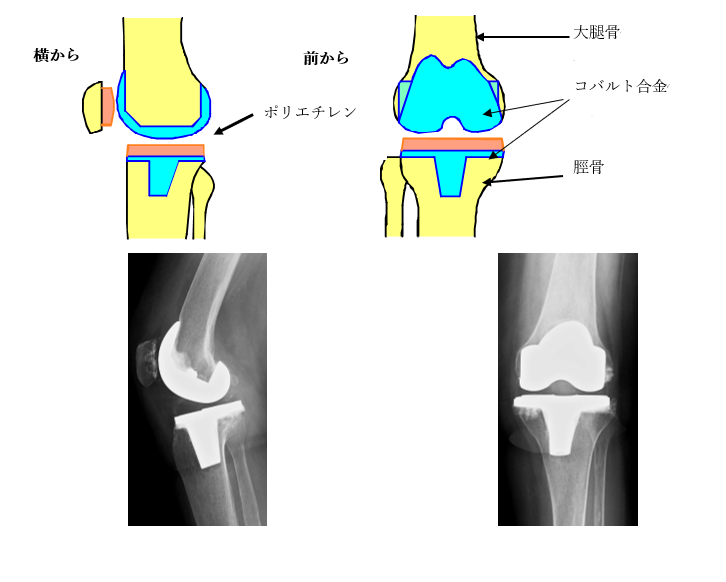

膝の関節の軟骨や骨が削れてしまうと、痛みのために歩行が困難となります。人工膝関節置換術は傷んだ関節を人工の関節ととりかえることにより、膝の痛みをとる手術です。手術は骨の表面(すり減った骨と軟骨)を切除し、金属に置き換えることにより行います。人工関節は下の図のように関節に設置されます。材質は骨と接している部分は金属(コバルト合金)で、その間にクッションの働きをするような高分子ポリエチレンをいれます。人工関節に置換することにより、歩行時などの骨や軟骨が削れる痛みを取り除くことができます。